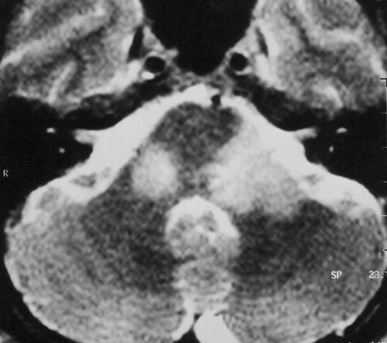

ЦНС поражают лейкемические очаги примерно в 30% случаев. Очаги могут поражать собственно вещество мозга, либо протекать по типу лейкозного менингита. Чаще такой тип течения наблюдается у детей при остром миелолейкозе.

Рост лейкемических очагов по опухолевому типу называют «гранулоцитарной саркомой». Очаги обычно возникают на границе белого и серого вещества.

При МРТ головного мозга очаг обычно изоинтенсивен коре мозга. Отёк при МРТ может быть выражен в разной степени. Внутри лейкемического очага, особенно при остром лейкозе, при МРТ головного мозга могут быть кровоизлияния, хорошо видимые на Т1-взвешенных МРТ. При МРТ головного мозга с контрастированием усиление сигнала слабое, неоднородное. Изредка лейкемические очаги вызывают тромбоз венозного синуса, имеющий характерные черты при МРТ головного мозга.

МРТ головного мозга. Очаги лимфолейкоза. Аксиальная Т2-зависимая МРТ.

При МРТ в СПб основную задачу у пациентов с подозрением на гранулоцитарную саркому мы видим в дифференциальной диагностики с другими очаговыми поражениями, особенно лимфомами. МРТ головного мозга при заболеваниях кроветворной системы еще необходимо для исключения инфекционных осложнений. Надо отметить, что в дифференциальной диагностике помогает выявление гранулоцитарных сарком в других местах - коже, орбите, пазухах носа, печени, в мягких тканях шеи, в средостении и легких.